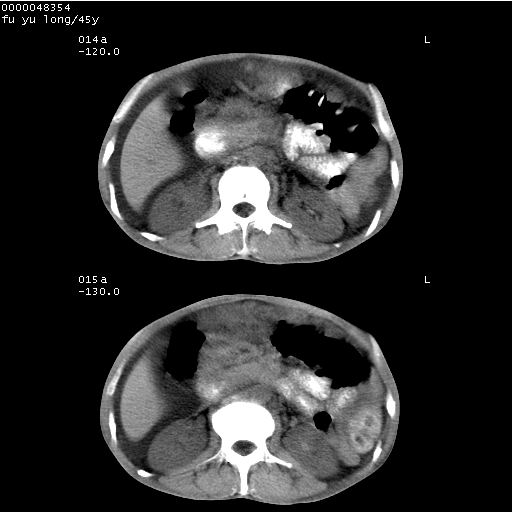

以下是引用医影拾贝在2008-5-30 2:38:00的发言:[br]气肿性胃炎、胃十二指肠溃疡、腹膜炎,考虑穿孔可能性较大

以下是引用lkc8963在2008-5-30 8:44:00的发言:[br]胃窦癌伴网膜(胃结肠韧带)/腹膜及腹膜后淋巴结转移.